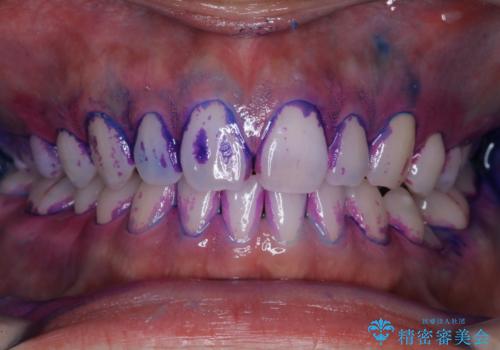

親知らずを抜いて1週間後にPMTC 歯のクリーニング

- 親知らずの抜歯後の約1週間後に抜糸(縫った部分の糸とり)で来院されました。その際、抜歯後は傷口が怖くて歯磨きが上手くできず、汚れや口臭が気になるためクリーニングも希望されました。

抜歯後は多少出血したり、違和感や痛みを感じたりすることがあります。そのため親知らずを抜いたり、外科的な処置をするといつも通りの歯磨きがしづらくなります。また、傷口の周りが心配で、歯ブラシをするのが怖くなるものです。抜歯後落ち着いたら、歯科医院にて専門の機械を使用しクリーニングをすることがおすすめです。抜歯前や後にPMTCを行うことで、お口の中の健康維持につながり、その後の感染・腫れ・口臭予防などになります。

親知らず抜歯後正常に治癒が進んでいれば1週間後から可能です。